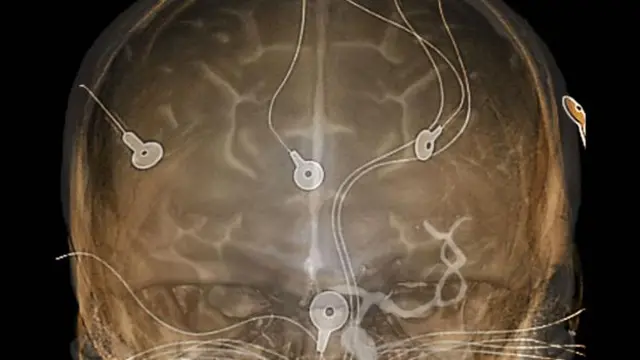

Fakat bu beyni eylem halinde görmeye yaramıyordu. Ancak 1920’lere gelindiğinde araştırmacılar beyindeki elektrik sinyallerini okumaya başlamıştı. Böylece canlı beyindeki elektriksel aktiviteye dair ilk bilgiler oluşmuş ve elektroensefalografi (EEG) tekniği geliştirilmişti.

Başlangıçta EEG çiftlerin evlilik için birbirine uygun eş olup olmadığını ya da suçluların beynini inceleme gibi ilginç nedenlerle kullanıldı.

Fakat daha sonra epilepsi hastalarının beyninde nöbet sırasında neler olup bittiğini anlamak amacıyla kullanıldı.

Dabin, müzenin deposunda saklanan bir <link type="page"><caption> EEG makinesi gösterdi</caption><url href="http://www.bbc.com/future/story/20151028-a-brief-history-of-our-desire-to-peer-into-the-brain" platform="highweb"/></link>. Bu makine beynin sinyallerini okumanın yanı sıra elektrik vererek onu harekete geçirmek amacıyla da kullanılıyordu. Fakat bu sinyaller tek başına beyni anlamaya yetmiyordu.